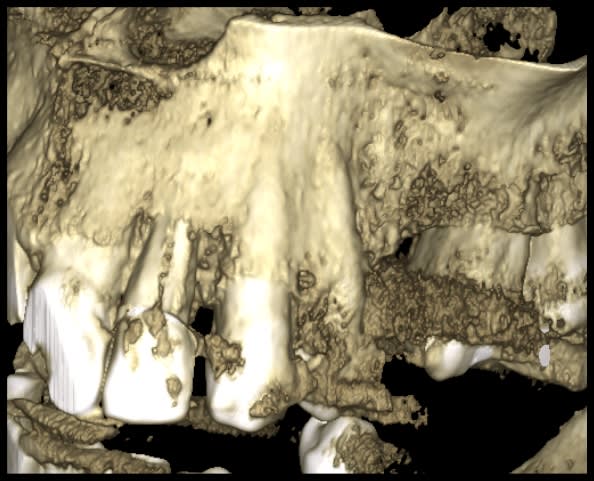

Marrant parce que cette fêlure sur 22, on ne la voit pas du tout sur la rétro, mais très bien sur la reconstruction 3D du CBCT

Jwjbelah9gpo9q1h8cqdm9j3kbi5 - Eugenol

Pevaeb5p7eph9oqexipq9lo1cuwa - Eugenol

Tu ne peux absolument pas conclure que ce qu’on voit ici est une fêlure. C’est plus vraisemblablement un artefact du au matériau canalaire.

Indépendamment de la remarque de dentarue (les reconstitutions 3D c'est dégueulasse et c'est compliqué de conclure quelque chose dessus. Seules les coupes sont fiables), c'est exactement ce que je disais: dans ton cas ta 2D ne montrait rien à cause du tenon. Mais si on en croit ton interprétation de la 3D, il y a déplacement des fragments et un espace visible en 3D, c'est plus une fracture qu'une fêlure à mon sens. Il faudrait peut être définir ces termes, quelqu'un sait s'il existe une vraie définition scientifique?

Il n'y a qu'en modifiant les niveaux sur la recoonstruction 3D qu'on la met en évidence.

J'appelerais cela une fracture bien contenue..

Mouais, ou un artefact comme dit par dentarue. La reconstitution 3D n'est à ma connaissance prévue que pour une visualisation d'ensemble, pas un diagnostic précis sur une zone limitée. La reconstruction extrapole des trucs entre les plans de coupe et n'est absolument pas fiable. Il n'y a qu'à voir tous les espèces de grumeaux qu'on voit systématiquement partout sur les images.

Une image comme ça moi je n'en conclus rien, je me fie aux symptômes (il semble quand même y avoir une perte osseuse vestibulaire bien plus marquée que sur les voisines qui pourrait signer la fracture) et je dépose pour contrôler visuellement avant de décider d'avulser.